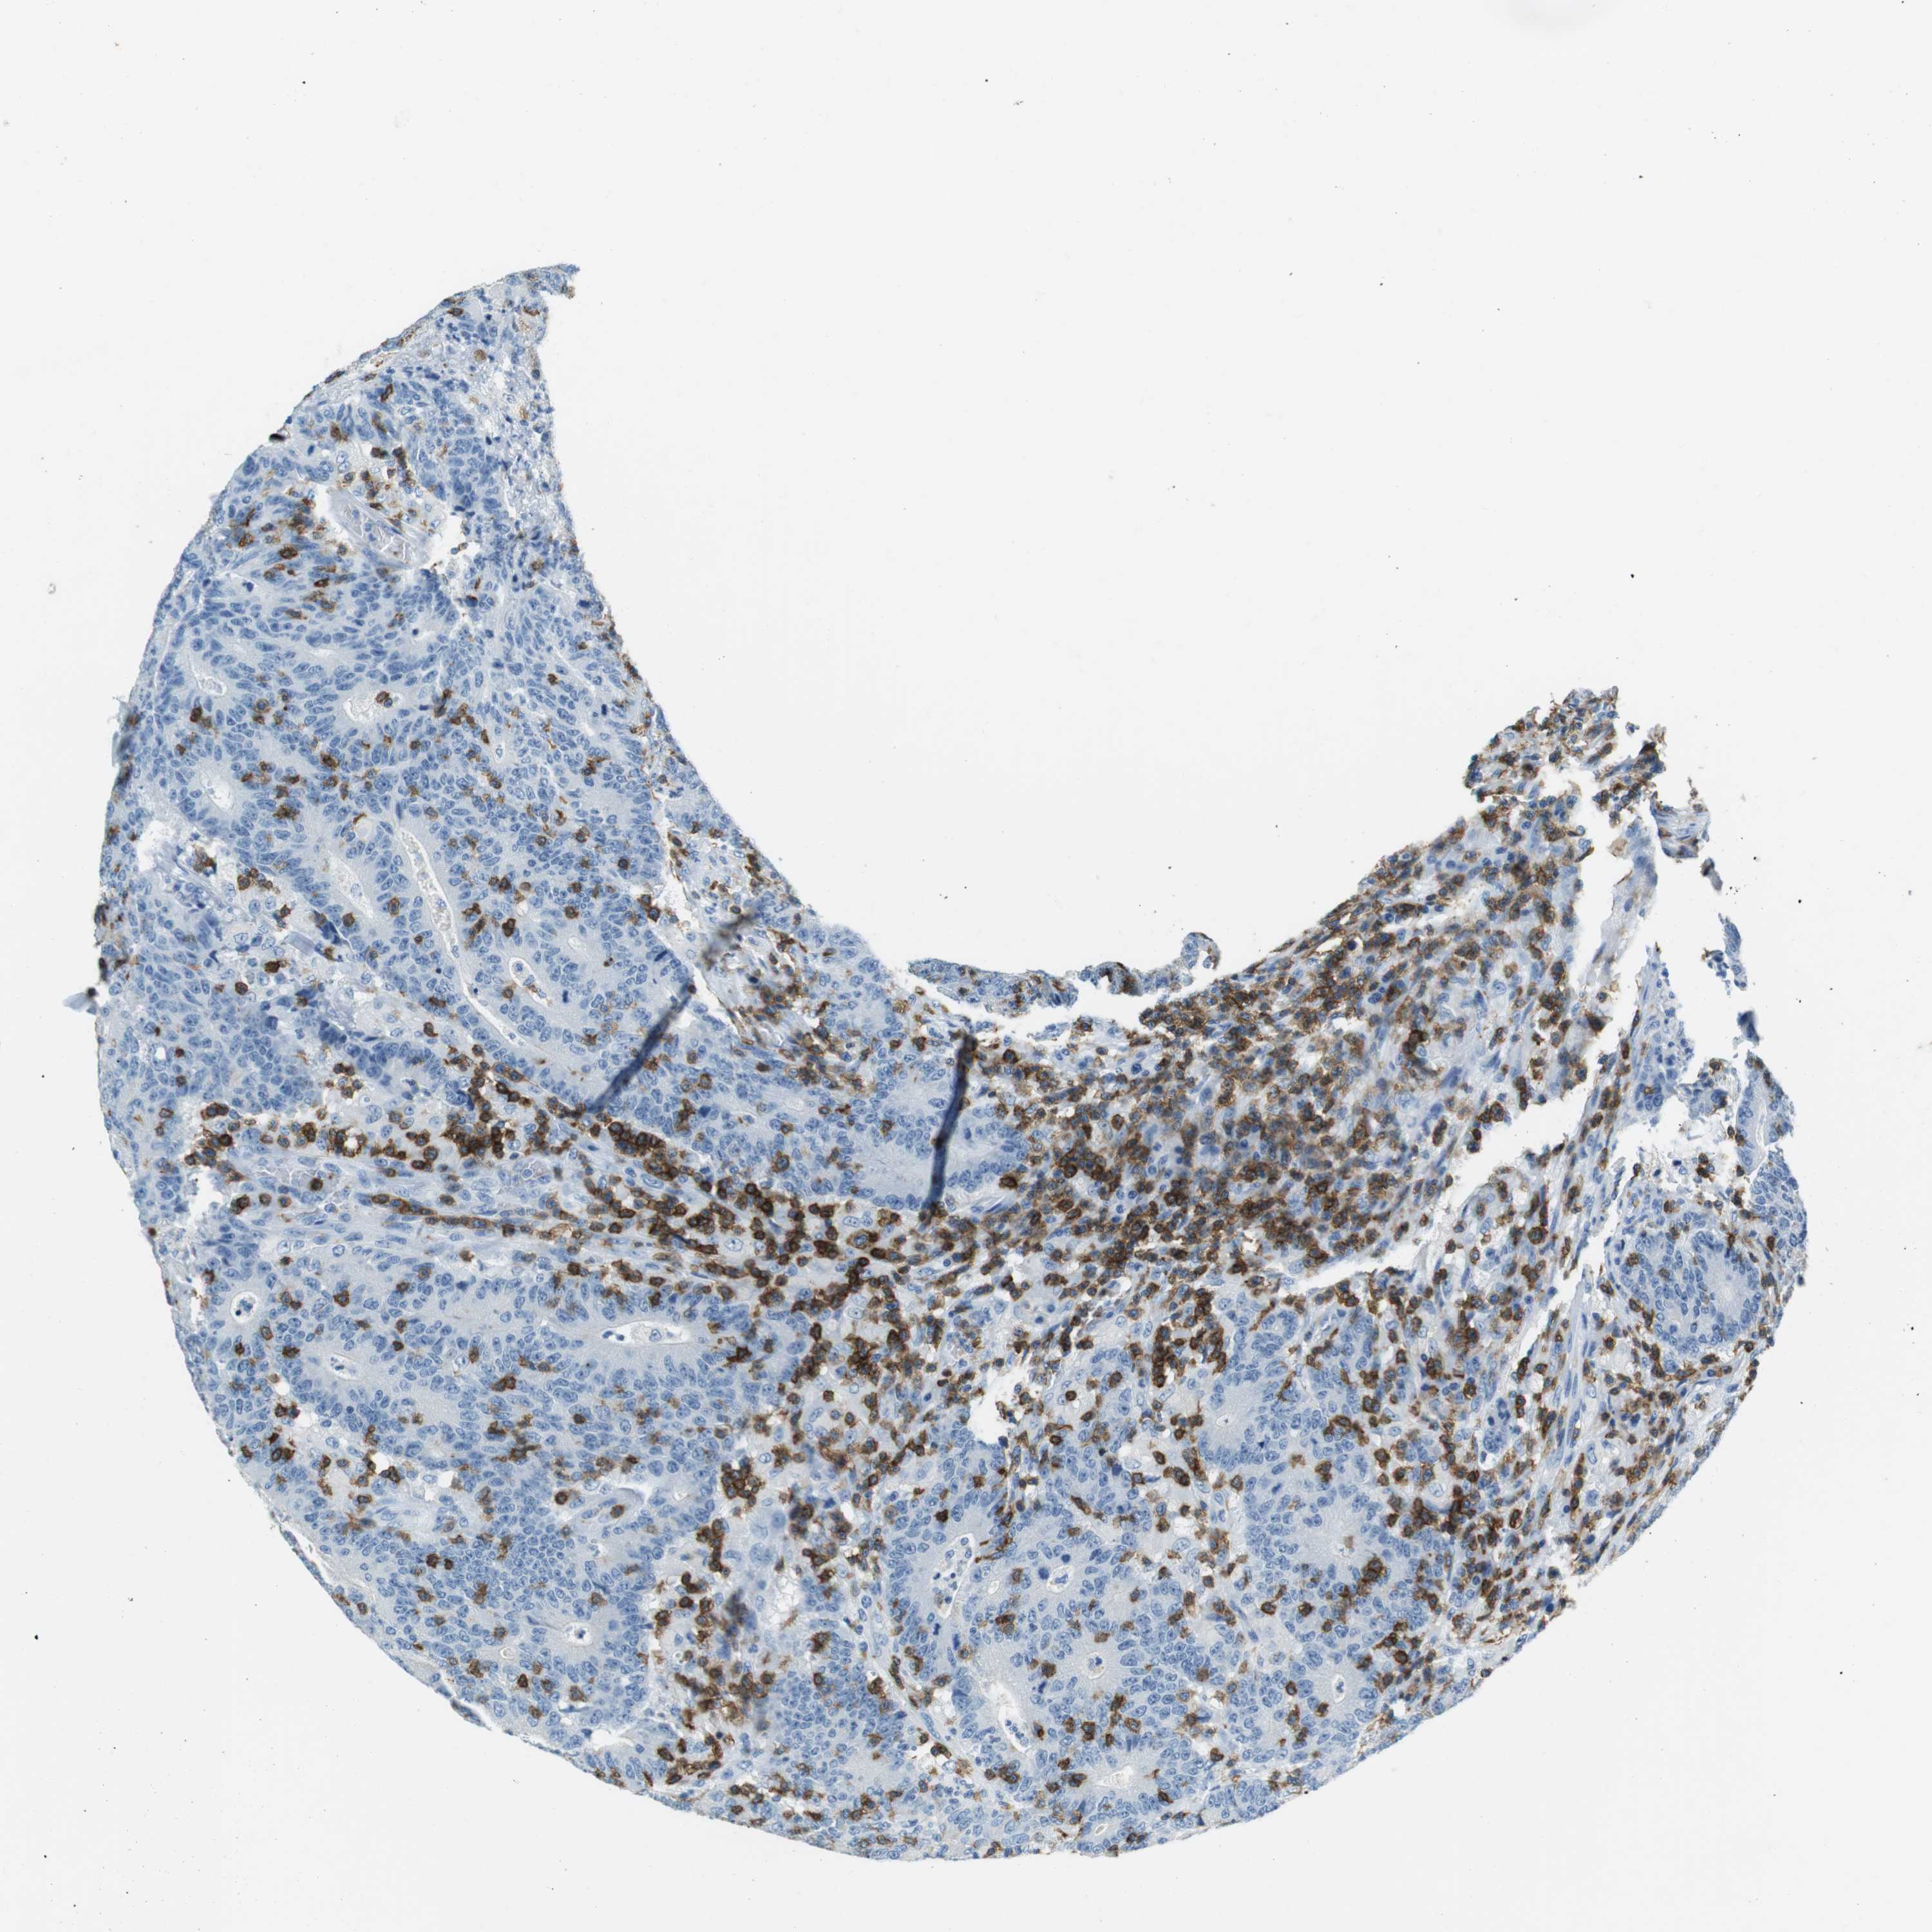

CANCER COLORECTAL CANCER Show tissue menu

Colorectal cancer

Human cancer

Colon adenocarcinoma